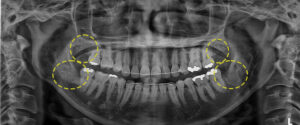

두 번째 환자분을 소개해 드릴께요.

위 환자분은 상악 좌측을 제외한

모든 곳에 사랑니를 가지고 계셨는데요.

파노라마 사진을 보시면 하악 좌측 사랑니는

치아가 수평 매복 되어 있고,

하악 우측 사랑니는 신경관을 물고

위치해 있는 것처럼 보였어요.

첫 번째 환자분에 비해 난이도가 더 높아보이죠?

CT 촬영 결과 다행히 신경관과 가까이

위치해있긴 하지만, 신경관을 물고 있는

상태는 아니라 발치가 가능했으며

신경관을 건드리지 않도록

주의가 필요했어요.

왼쪽 먼저 발치한 후 잇몸이 아물고 나면

반대쪽 상, 하악을 발치하기로 했으며,

마찬가지로 양쪽 모두 잇몸을 절개한 후

치아를 쪼개어 발치를 진행했어요.

발치 후 파노라마 사진을 보시면

깔끔하게 발치된 모습을 보실 수 있어요.👀